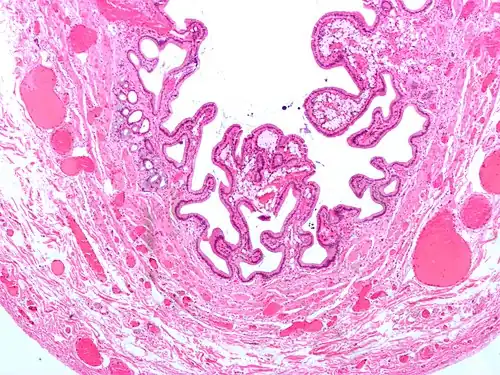

Micrograph of cholesterolosis of the gallbladder -